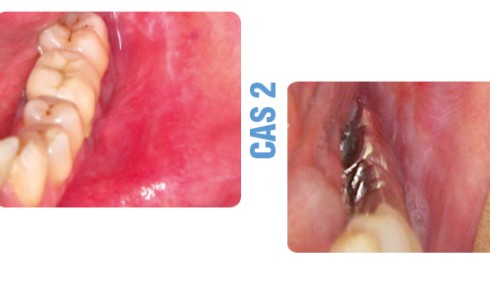

Article réservé à nos abonnés Deux tumeurs palatines inhabituelles

CAS 1 Motif de la consultation. Patiente âgée de 57 ans venant consulter pour une lésion palatine chronique, peu douloureuse,...